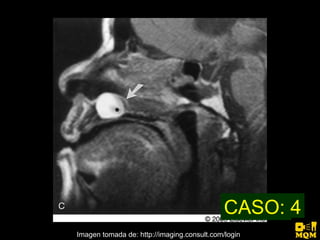

El quiste nasopalatino es un quiste embrionario situado en la línea media en la parte anterior del paladar, que se origina de los restos del conducto nasopalatino. Generalmente aparece entre los 40-60 años y se presenta como un aumento de volumen blando y no doloroso entre los incisivos centrales superiores que puede causar divergencia radicular. Las características radiográficas incluyen una lesión radiolúcida, bien delimitada y de forma redondeada u ovalada que cruza la línea media maxilar.